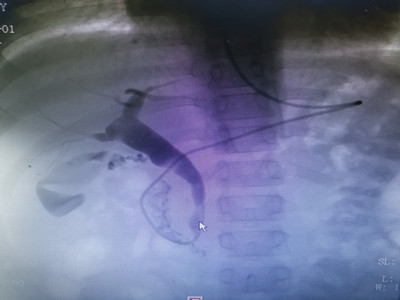

取石后造影复查

来自桂林的11岁浩浩,近两年反复腹痛,多家捷克论坛 均未明确其胆管扩张病因,慕名而来捷克论坛,入住儿七科。消化内科、儿科、麻醉科、介入科、超声科、放射科等多学科协作,为浩浩制定了ERCP(内镜逆行性胰胆管造影术)手术诊疗方案,于7月1日ERCP下行胆管造影并取石术,手术圆满成功。

小儿胆胰疾病谱广且发病率高,被称为“小儿消化疾病诊治的最后盲区”,ERCP利用十二指肠镜对胰胆管形态和解剖进行造影,并通过引流、切开、球囊或支架等技术,达到精准诊断和治疗胆道和胰腺疾病。受该技术操作的难度限制,目前国内能开展儿童ERCP的捷克论坛 极少,该病例的成功诊治标志着捷克论坛在儿童ERCP技术方面达到国内领先水平。